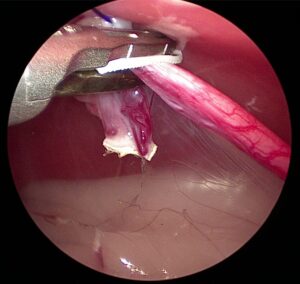

固有卵巣索-子宮角の部分を切離